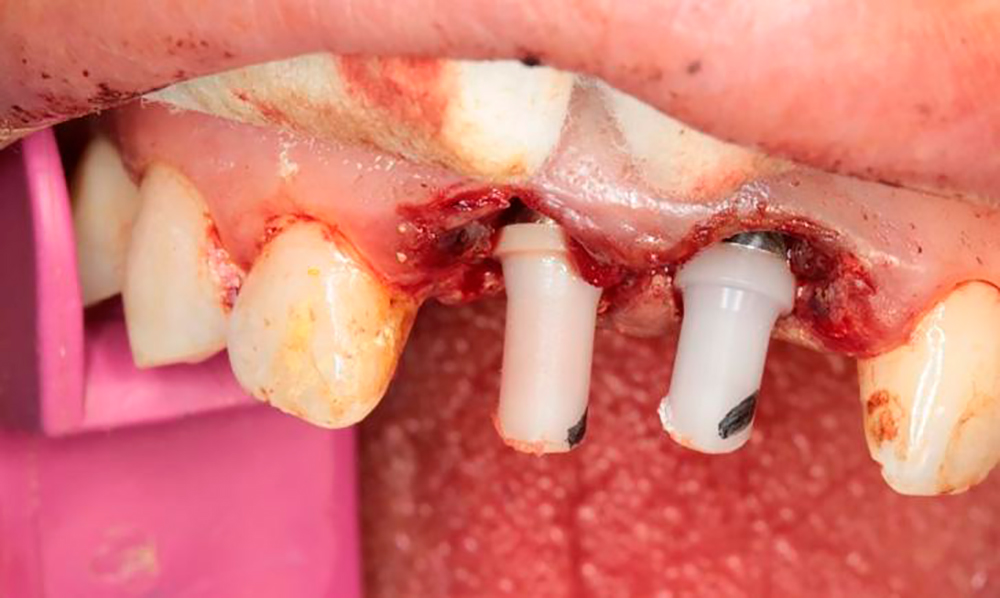

Premium Spiral Implants placement

Syntoss bone graft and Zenoss matrix membrane placing

DSI Angulated multi-unit abutments fixation